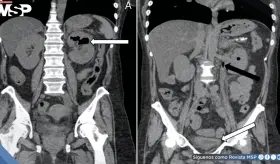

La compresión de la arteria coronaria principal izquierda (LMCA) por dilatación de la arteria pulmonar representa una complicación subdiagnosticada de la hipertensión pulmonar severa, con prevalencia del 6%.

El caso destaca la importancia del reconocimiento temprano mediante tomografía computarizada y el manejo agresivo con drenaje percutáneo y antibioticoterapia de amplio espectro.